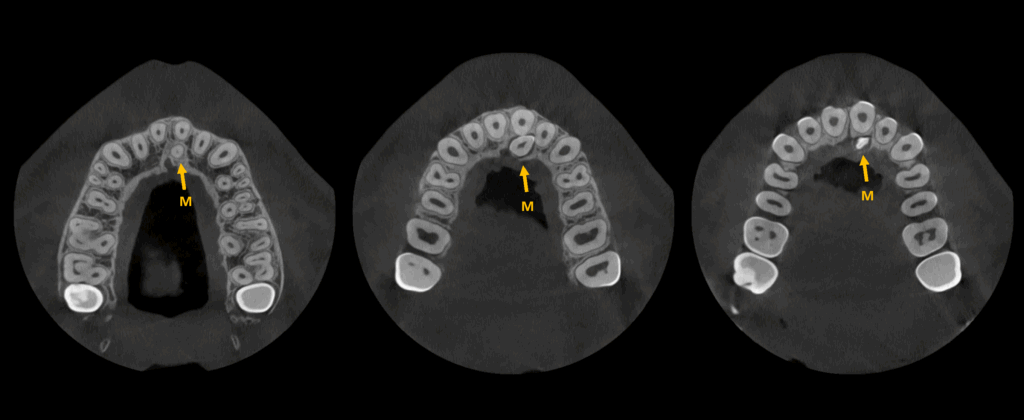

En el estudio complementario mediante tomografía computarizada de haz cónico (TCHC), se identifica una pieza dentaria supernumeraria (M) en posición palatina con respecto a la raíz de la pieza 21. La corona de esta estructura se encuentra en contacto directo con la superficie radicular de la pieza 21, como se evidencia en los cortes transaxiales.

CORTES AXIALES

CORTES TRANSAXIALES